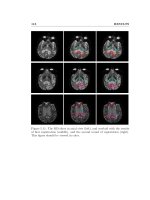

<i>sau 15 phút, (d) sau 30 phút. ... 134 </i>

5.2.2. Thử nghiệm in-vivo đánh giá khả năng ứng dụng hệ chất lỏng từ tính nano Fe<small>3</small>O<small>4</small> làm thuốc tương phản trong chẩn mô bệnh ung thư bằng kỹ thuật cộng hưởng từ MRI <i>trên động vật ... 130</i>